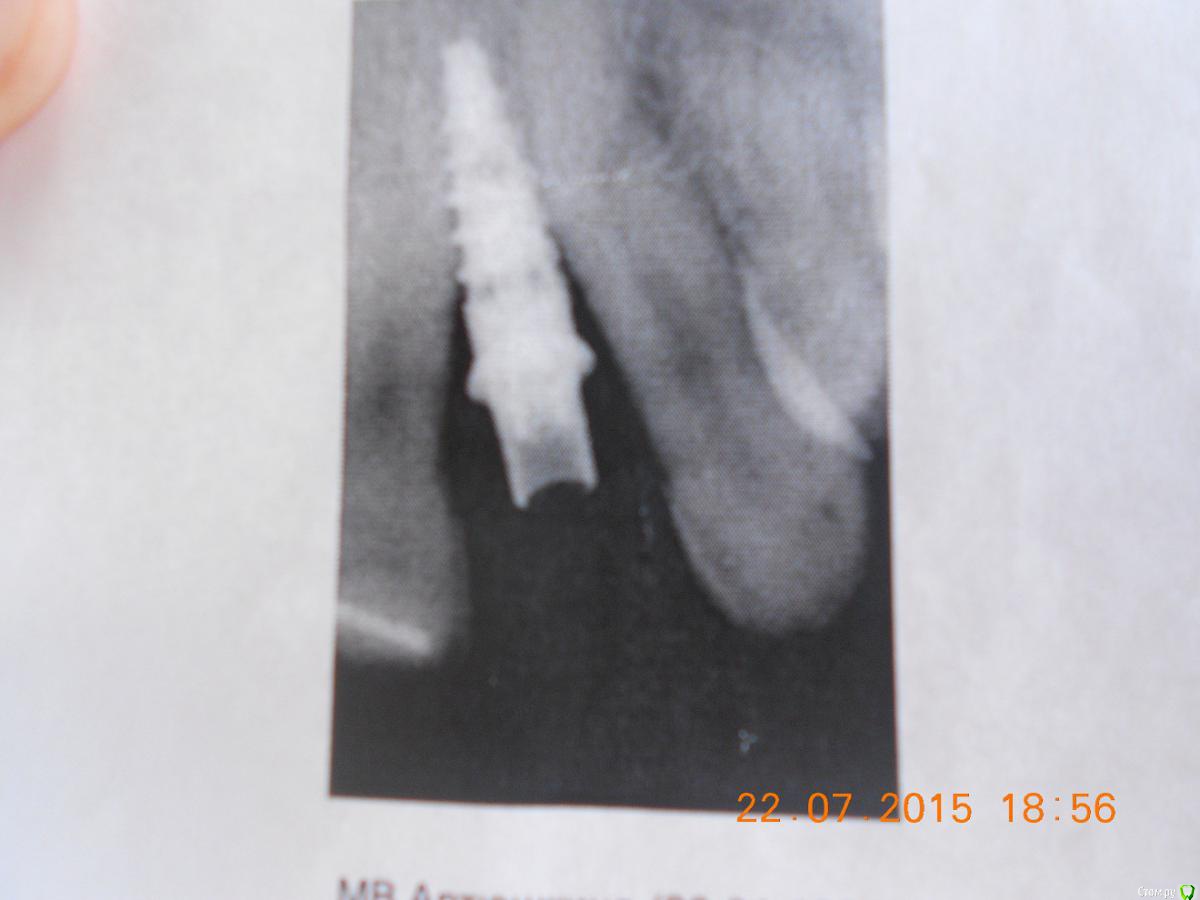

holodova.viktori Опубликовано 22 июля, 2015 Поделиться Опубликовано 22 июля, 2015 Добрый день, прошу помочь принять решение,что делать с имплатном.Поставили на ВЧ два импланта в октябре. Операция вроде бы прошла успешно, ничего не беспокоило. Через 4 мес. установили формирователь десны, проде бы тож все нормально было (снимки прилагаю).Еще через 2 недели отправили к ортопеду. И вот тут когда стал он выкручивать формирователь- стало больно очень-очень внутри кости , итог-имплант выкрутили. На второй имплант установили временную коронку и я с ней отходила ок. 3мес.,вокруг десны возникло локальное воспаление-отправили к пародонтологу,он к хирургу опять,хирург ничего критичного в импланте не увидел.Воспаление прошло-метрогилом мазала,календулой полоскала. И вот когда ортопед стал выкручивать временную коронку-стало опять больно,боль внутри кости опять.Послали на снимки. Хирург посмотрел снимки, потрогал зуб(временный кот), грит наблюдается убыль кости и подвижность имплатна 1 ст. И сейчас предлагает либо не трогать ничего и ходить с временной коронкой столько-сколько прохожу (грит от 2 мес. до неск.лет, те вопрос выпадения импланта-эт вопрос времени просто), либо удалять имплант.Консультировалась с несколькими др. хирургами они грят-необх.откручивать временную коронку и смотреть что с имплантом-выдерживает ли он нагрузку или подвижен, ели подвижен-удалять однозначно, ждать 6-9 мес. пока восстановится объем костной ткани и потом решать что делать дальше.И пока ходить со съемными протезами.И все они грят,что изначально места было недостаточно,для имплантов и есть ошибки хирурга на стадии планирования операции и выбора р-ра имплантов.Очень прошу прокомментировать ситуацию. Ссылка на комментарий

krokomot Опубликовано 22 июля, 2015 Поделиться Опубликовано 22 июля, 2015 Я так понимаю боковые резцы у вас всю жизнь отсутствовали.По мне имплант слишком близко расположен к корням соседних зубов. Прогноз у него весьма сомнительный. 1 Ссылка на комментарий

chervoncevdaniil Опубликовано 22 июля, 2015 Поделиться Опубликовано 22 июля, 2015 А почему есть риск потерять соседние зубы? Я просто тож склоняюсь к удалить,восстановиться и потом решить,что делать.Для установки имланта должны быть определенные условия,в частности расстояние до соседних зубов МИНИМУМ 1.5 мм,если этих 1.5 мм нет,то либо это расстояние нужно создать(как вариант ортодонтия),либо имплантация не проводится.Никакой подвижности быть не должно,там сейчас воспалительный процесс,который ведет к убыли кости,мой совет вам имплант убирать,чуда не произойдет и подвижный имплантат не станет устойчивым,нужно начинать лечение заново,как бы это не печально звучало 3 Ссылка на комментарий

holodova.viktori Опубликовано 29 июля, 2015 Автор Поделиться Опубликовано 29 июля, 2015 Добрый день, удалила имплантик и у меня снова возник вопрос.Хирург(ставивший и удалявший имплант) после удаления настаивает на том,что имплант стал правильно, места было достаточно, и что причина в индивидуальных особенностях костной ткани,ну что-то типо того,что кость не смогла удержать имплант.Вопрос,такое реально бывает, Вы сталкивались с такими ситуациями в своей врачебной практике?Сторонние хирурги к которым я обращалась за очной доп.консультацией, в качестве причины однозначно называли недостаточность места и плюс(ну в качестве отягчающего обстоятельства) гипотетически возможная некоторая подвижность зубов после снятия брекетов(что зубы могли выталкивать имплант,как-то так я поняла),Имплантацию проводили в брекетах.Сняли после установки формирователя. Помогите разобраться пож. Ссылка на комментарий